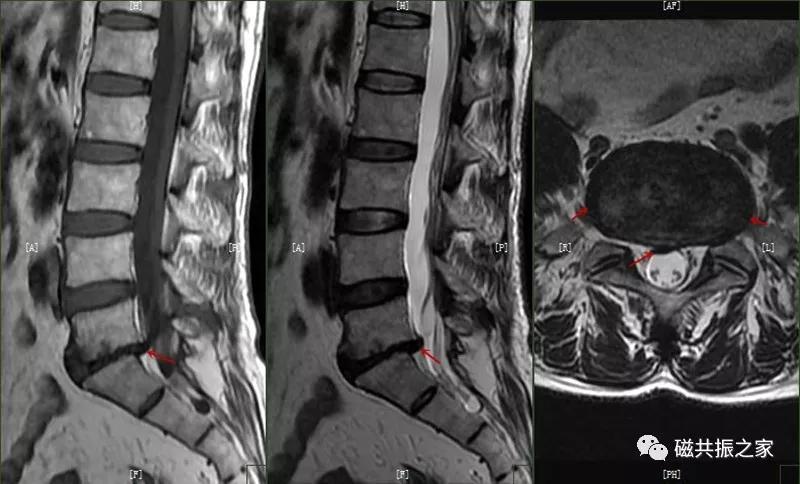

椎间盘突出:当纤维环的完整性受到破坏时,在水平方向的应力作用下,椎间盘向后或侧后突出,对于的硬膜囊、神经根及脊髓受压。

95%的椎间盘突出为中央型或旁中央型,5%的椎间盘突出为椎间孔型和椎间孔外型(图片来自网络),拓展阅读椎间盘突出表现。

椎间盘脱出:椎间盘突出进一步发展,突出的髓核调入椎管内或与突出部分分离,先后移位形成脱出,甚至髓核可脱离进入椎管内,脱出的髓核在T1WI上呈低、等信号,在T2WI上呈中、高信号,需与椎管占位及滑膜囊肿鉴别。